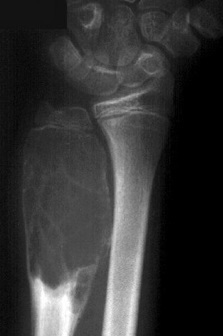

3

Q

Qual diagnóstico?